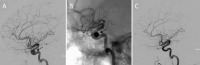

Neurovaskuläre Therapieoptionen bei komplexen Aneurysmen der Arteria carotis interna // Neurovascular therapeutic options in complex intracranial aneurysms

Journal für Neurologie, Neurochirurgie und Psychiatrie 2021; 22 (3): 128-134 Volltext (PDF) Summary Praxisrelevanz Abbildungen